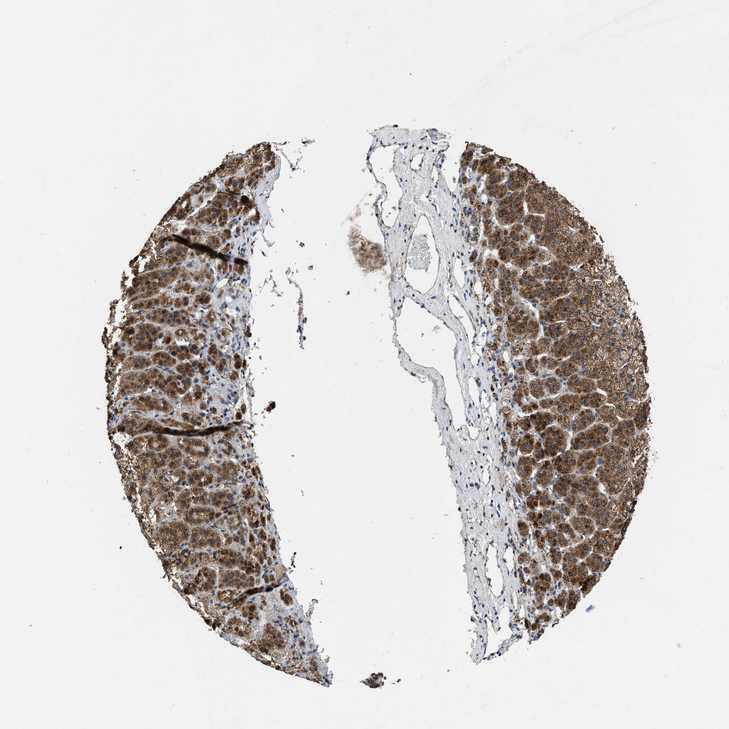

ADRENAL GLAND - Antibody stainingi

Antibody staining in the annotated cell types in the current human tissue is reported as not detected, low, medium, or high, based on conventional immunohistochemistry profiling in selected tissues. This score is based on the combination of the staining intensity and fraction of stained cells.

Each image is clickable and will lead to virtual microscopy that enables deeper exploration of all samples and also displays staining intensity scores, fraction scores and subcellular localization as well as patient and tissue information for each sample.

Antibody HPA018483Antibody HPA019081Antibody HPA021152

Glandular cells MediumMediumMedium